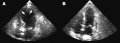

(A) Echocardiogram showing dilatation of the left ventricle in the acute phase (B) Resolution of left ventricular function on repeat echocardiogram six days later- ECG showing sinus tachycardia and non-specific ST and T wave changes from a person with confirmed takotsubo cardiomyopathy

- Echocardiogram showing the effects of the disease[56]